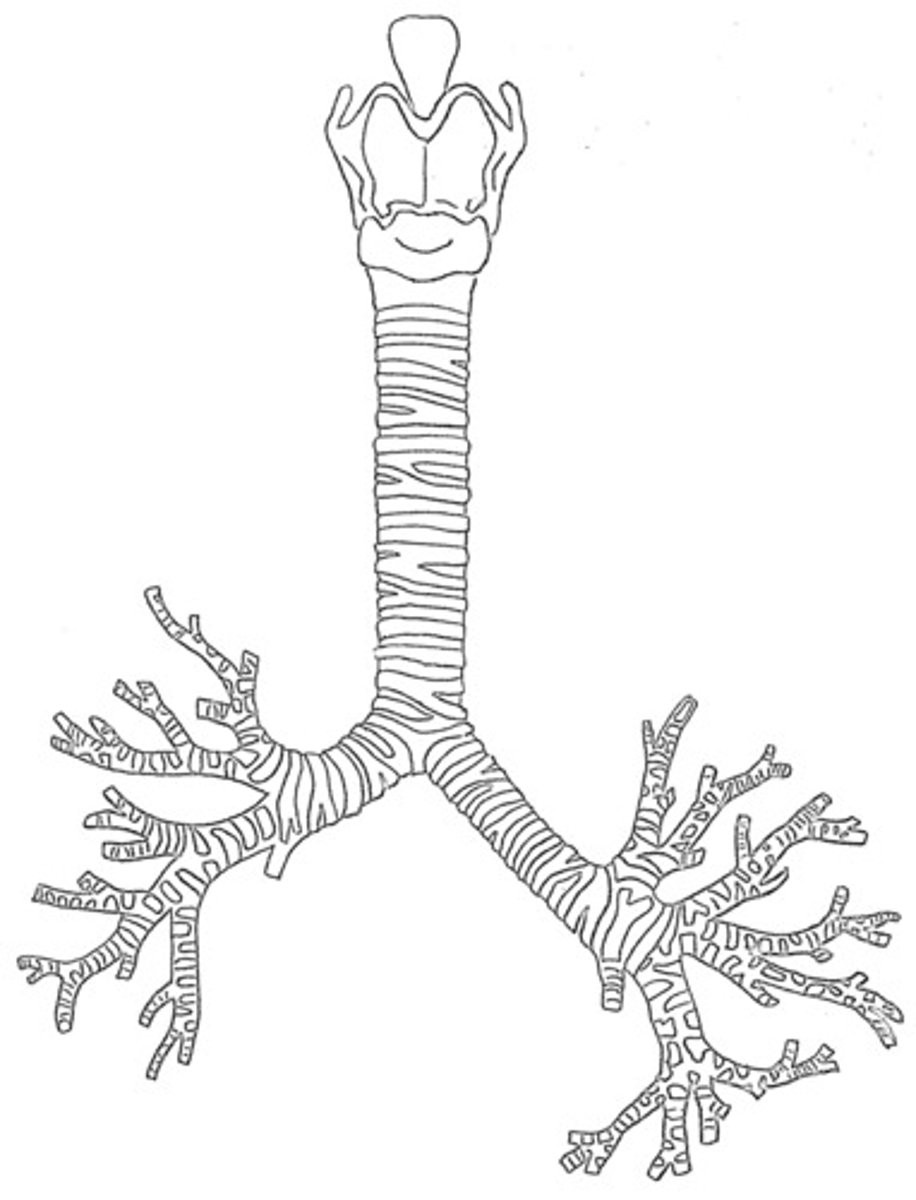

trachea

tube composed of cartilaginous rings and supporting tissue that connects the lung bronchi and the larynx; provides a route for air to enter and exit the lung

bronchus

tube connected to the trachea that branches into many subsidiaries and provides a passageway for air to enter and leave the lungs

bronchial tree

collective name for the multiple branches of the bronchi and bronchioles of the respiratory system